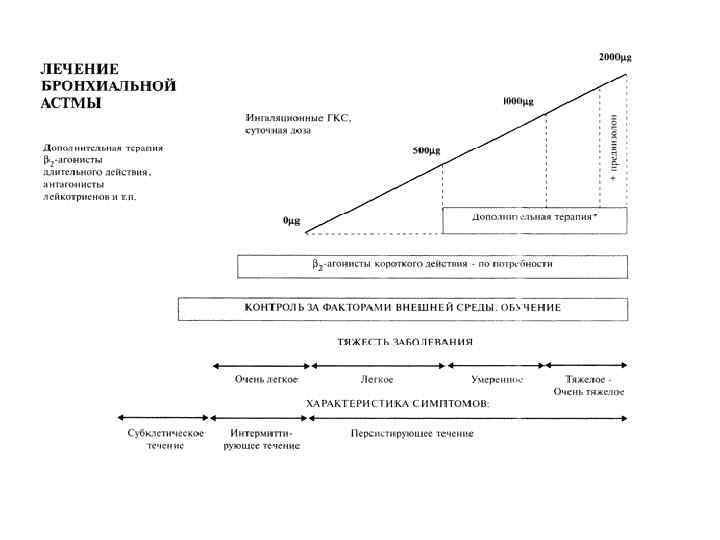

2. Степень тяжести течения (ступени): – – Ступень I – интермиттирующая астма (эпизодическая): симптомы - реже 1 раза в неделю; обострения заболевания короткие (от нескольких часов до нескольких дней); ночные симптомы менее 2 раз в месяц ; ОФВ 1 (ПСВ) >80% от нормы, суточные колебания < 20%. Ступень II - легкая персистирующая астма: симптомы проявляются от 1 раза в неделю до 1 раза в день; ночные симптомы возникают более 2 раз в месяц; обострения заболевания нарушают активность и сон; ОФВ 1 (ПСВ) >80% от нормы, суточные колебания 20 - 30%. Ступень III - персистирующая астма средней тяжести: ежедневные симптомы; обострения заболевания нарушают активность и сон; ночные симптомы возникают более 1 раз в неделю; необходим ежедневный прием бета – 2 агонистов короткого действия; ОФВ 1 (ПСВ) от 60 до 80% от нормы, суточные колебания более 30%. Ступень IY - тяжелая персистирующая астма: постоянные симптомы; частые обострения заболевания нарушают активность и сон; частые ночные симптомы; физическая активность ограничена, необходим ежедневный прием бета – 2 агонистов короткого действия; ОФВ 1 (ПСВ) < 60% от нормы, суточные колебания более 30%.

Степени тяжести